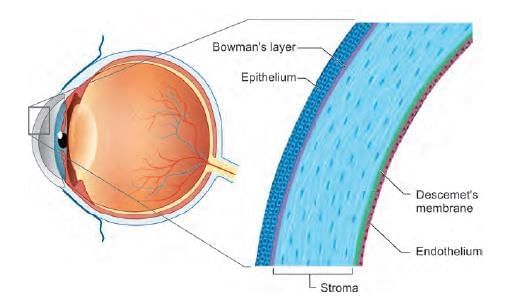

Which layer maintains hydration of corneal stroma? (NEET-PG 2020p)

Identify the marked layer in the given histological section: (AIIMS Nov 2019)